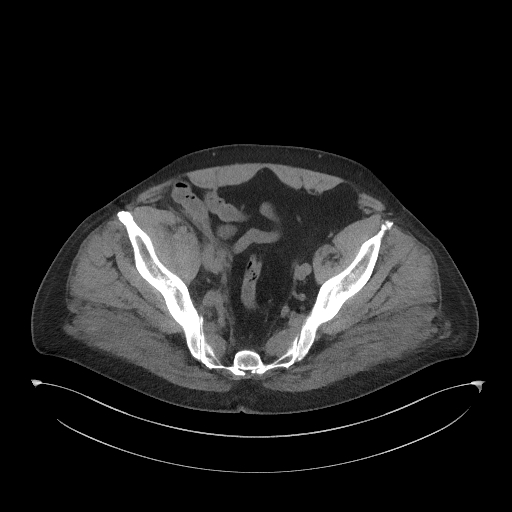

Figura 1: reconstrucție oblic axială din achiziție CT fără contrast posttraumatic imediat

Discuţie caz nr 134: Pe imaginile achiziționate fără substanță de contrast se remarcă creștere marcată de volum a muschiului ilio-psoas drept în două treimi distale cu evidențierea unei plaje întinse cu densități sangvine ce sugerează prezența unui hematom posttraumatic; nu se evidențiază traiecte de fractură. Achiziția de control după 22 de luni evidențiază reducerea grosimii corpului muscular ilio-psoas drept cu încărcare grăsoasă care, pe alocuri, afectează aproape complet corpul muscular.